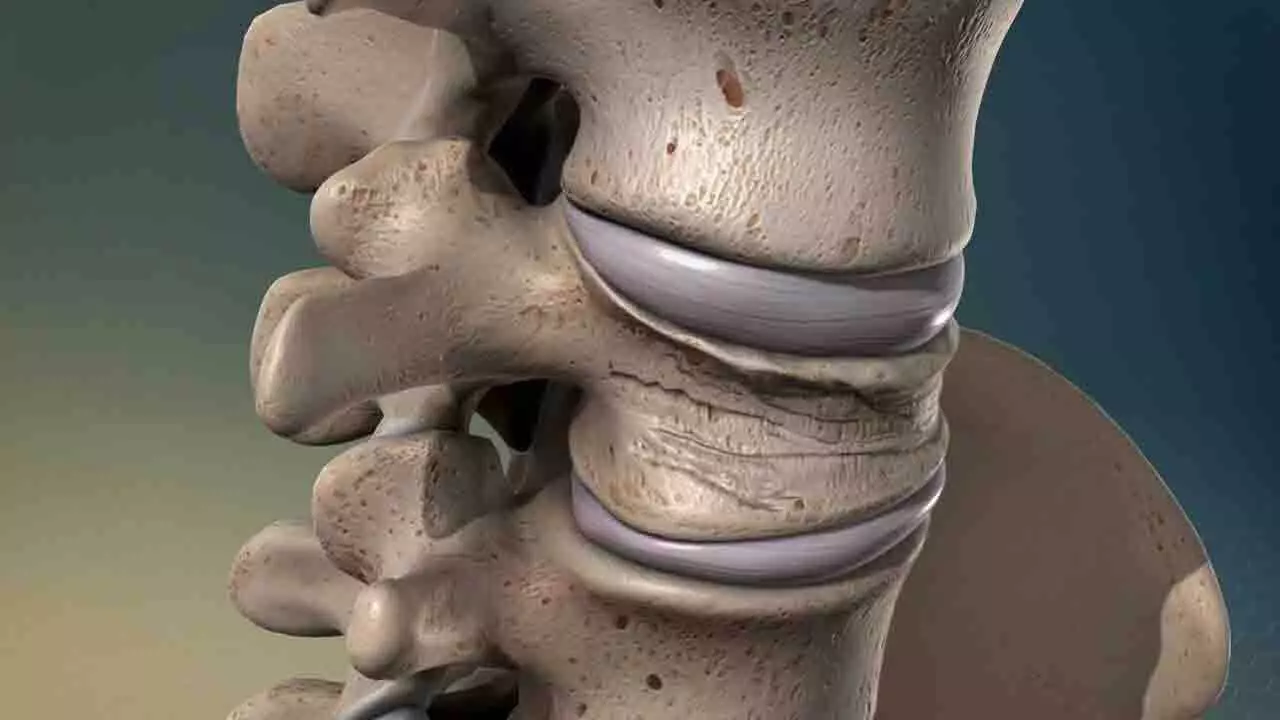

شکستگی فشاری نوعی شکستگی ناشی از فشار در استخوان مهرههای ستون فقرات است که در آن بخشی از مهره خرد شده و ارتفاع آن کاهش مییابد. این شکستگیها به سه نوع اصلی تقسیم میشوند:

- برست (Burst fracture): مهمترین و جدیترین نوع شکستگی فشاری است؛ چرا که علاوه بر فروریختن مهره در چند جهت، ممکن است قطعات خردشده به نخاع یا بافتهای اطراف فشار بیاورند و موجب بیثباتی ستون فقرات یا آسیب عصبی شوند. این نوع شکستگی به درمان فوری نیاز دارد.